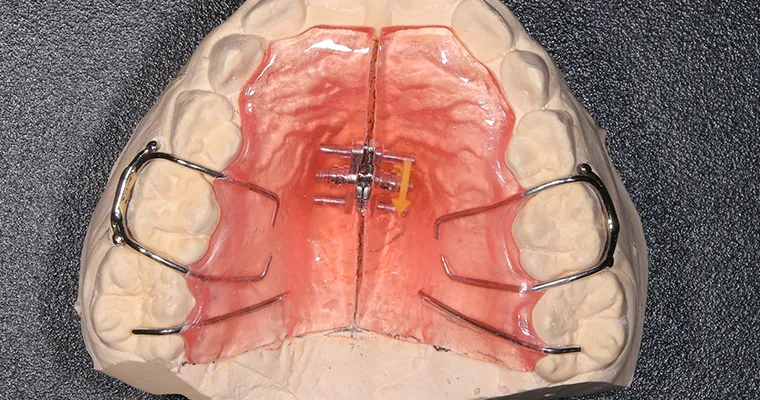

使用矯正装置 上

| 主訴 | 歯並びが悪い 乳歯と永久歯が重なっている 歯がまっすぐはえてこない |

|---|---|

| 治療期間 | 6-7ヶ月 |

| 治療費 | 440,000円(税込) ※調整、器具、治療後にお渡しするEFLine(矯正後の後戻りを防ぐ器具)も全て込みでの金額となっております。 |

| 治療内容 | 拡大床矯正 EF Lineで筋機能療法 |